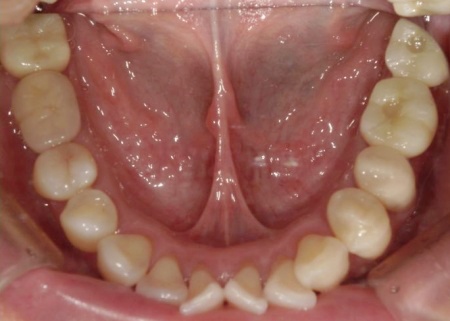

拝見したところ、左上の抜歯部周辺は歯を支える骨が溶ける「骨吸収」が進行し、隣接している歯を含めた複数の歯がひどくグラグラしており、温存が困難です。

噛み合わせも安定していなかったため、このままでは残っている歯への負担が増加し、歯の揺れやさらなる噛み合わせの悪化につながるリスクがあります。

また、右下奥歯には、両隣の歯を土台にして橋を渡すように欠損部を補う被せ物「ブリッジ」が装着されていました。

右下奥歯は2本欠損しており、親知らず(第3大臼歯)と手前の奥歯(第2小臼歯)の2本でブリッジを支えていますが、これは親知らずに過度な負荷がかかる構造です。

親知らずはすでに大きく傾いており、こちらも温存が難しいため、ブリッジを除去してから親知らずを抜く必要があります。